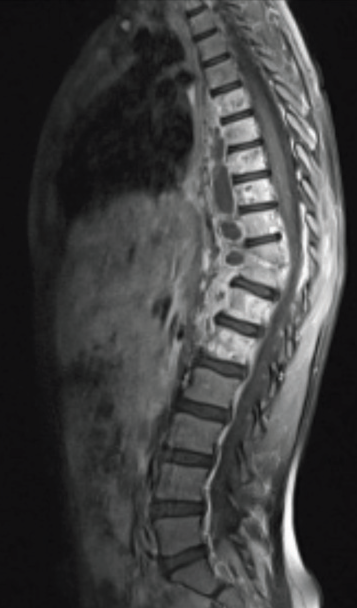

Omurga enfeksiyonuna ait MR görüntüsü

Ortopedik enfeksiyonların tanısı doğru ve erken bir şekilde konulmalıdır. Tanı için kan testleri, görüntüleme yöntemleri (röntgen, MR, sintigrafi) ve enfekte dokudan alınan örnekler gibi yöntemler kullanılır. Bu yöntemler enfeksiyonun yerini ve şiddetini belirlemede yardımcı olur.